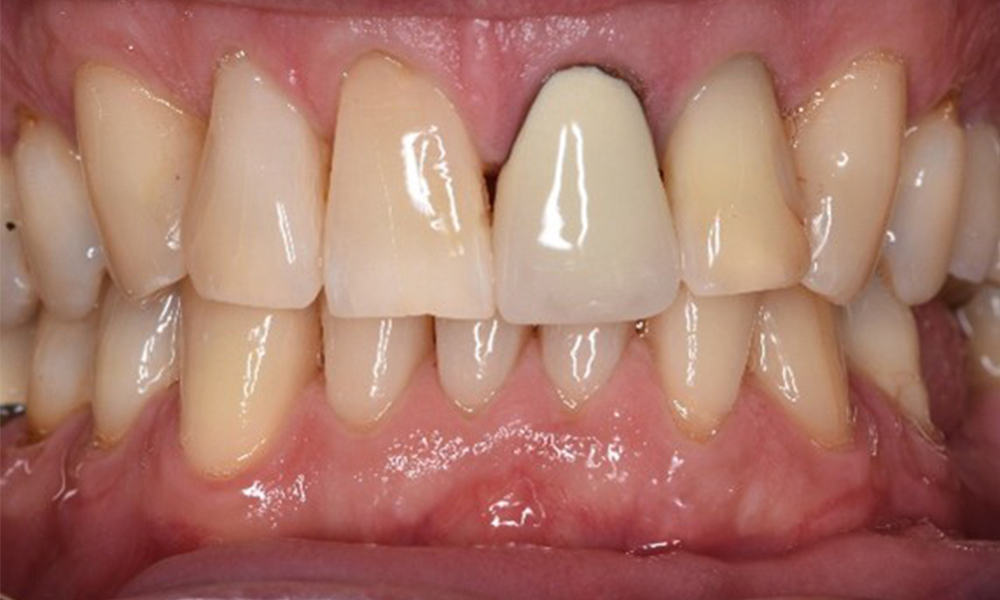

In the medical history, the 55-year-old patient states that he has no systemic disease and is not taking any medication. The patient’s lifestyle is similarly unremarkable. The patient has a few tooth restorations and two implants (2nd and 4th quadrants). On the basis of current findings, gingivitis is identified in an otherwise stable periodontal condition on the reduced periodontium (stage III, grade A).

Previous treatments: dental restorations (non-precious metal/ceramic blend), two implants (2nd, 4th quadrants)